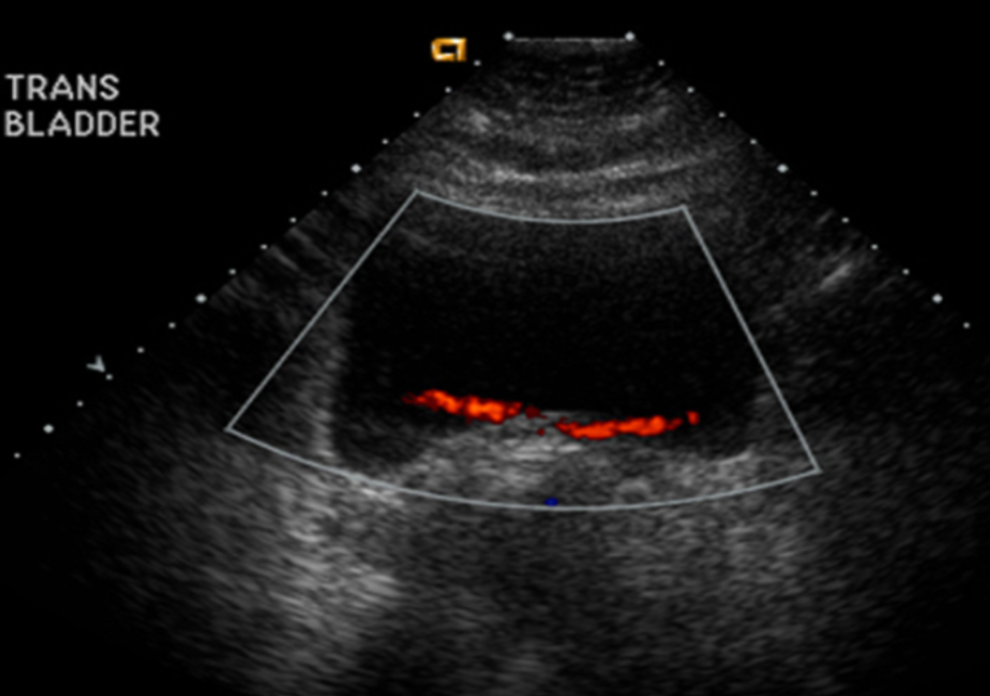

(Carotid, thyroid, liver, abdomenal aorta, pancreas, kidneys, gallbladder, aorta, spleen, gall bladder, liver, lower legs, posterior calf, bladder, and prostate)

(Carotid, thyroid, liver, abdomenal aorta, pancreas, kidneys, gallbladder, aorta, spleen, gall bladder, liver, lower legs, posterior calf, bladder, and uterus)

Whole body ultrasounds provide a non-invasive, painless, imaging option, allowing for the assessment of various organs without exposure to radiation.

This screening can help identify abnormalities such as tumors, cysts, or vascular issues at an early stage, potentially improving treatment outcomes. Our general screening exams include: breast, thyroid, kidneys, liver, spleen, aorta, pancreas, and calf veins.

Additional screening may include prostate and uterus.